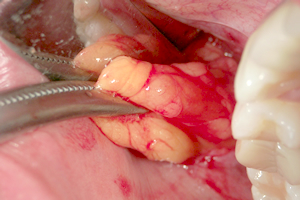

バッカルファットパット直下に至ると、卵黄色の薄い膜に包まれたバッカルファットを目視できます。直視下において、除去すべき脂肪を一塊に除去します。

写真で見る「バッカルファットを除去する様子」

④ バッカルファット

の露出